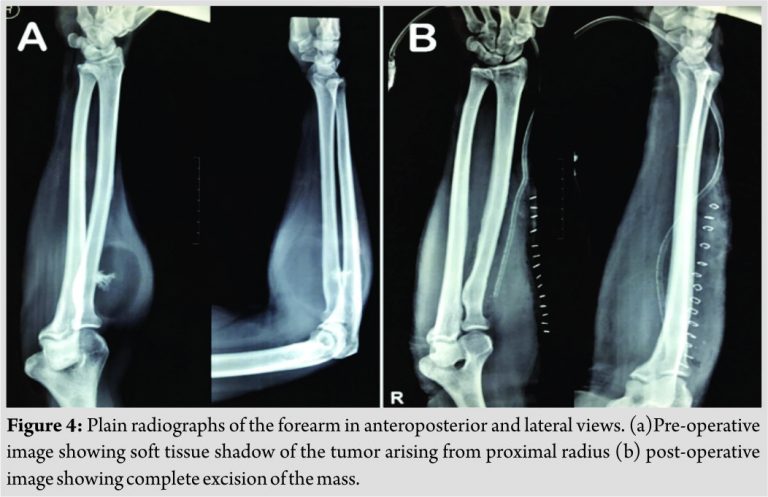

Histological examination confirmed the diagnosis of encapsulated lipoma except for its attachment at the bone. Postoperatively, he had a full range of motion at the elbow (flexion:0–145°, supination:0–85°, and pronation:0–90°) and the wrist. The patient was followed-up for 2 years and was found to have a complete range of motion with no radiological or clinical evidence of recurrence of the tumor (Fig. 4).